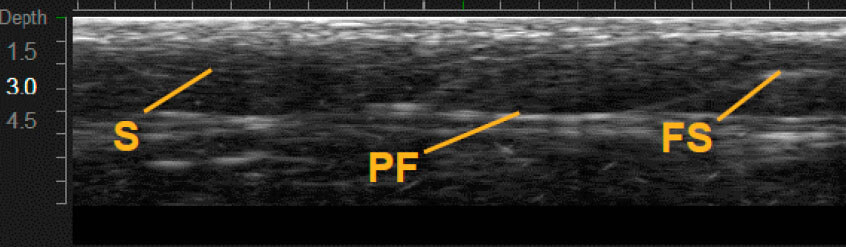

Приклади варіантів структури шкіри між індивідуальними пацієнтами 1,12

Візуалізація в реальному часі є основою Ultherapy®

MFU-V дає змогу лікарям точно бачити і враховувати всі анатомічні особливості в індивідуальному плані лікування, який буде ефективним.1